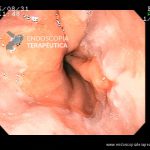

Esofagite Erosiva por Doença do Refluxo

- Esofagite Los Angeles A